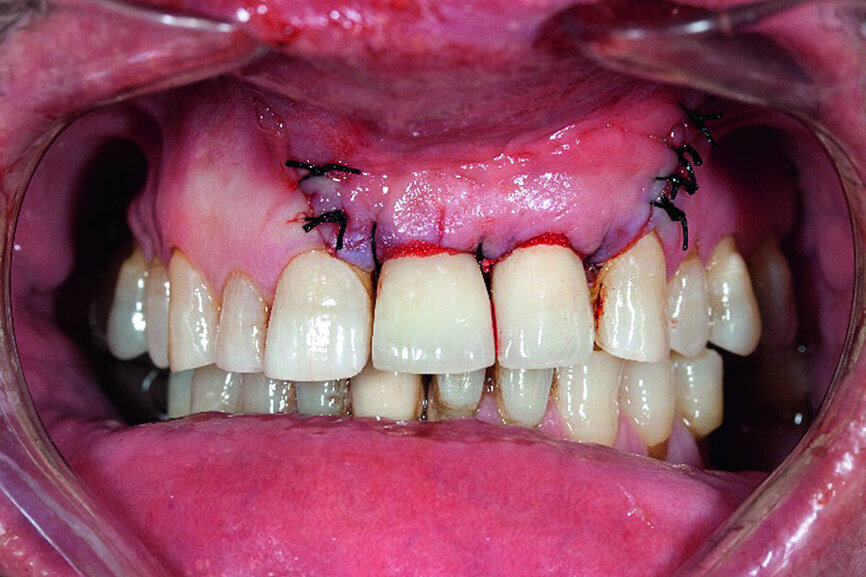

Finally, the surgical area was covered with the bioresorbable membrane, and the flap was re-adapted with interrupted sutures in order to achieve a complete and impermeable wound closure (Fig. 8). The radiograph taken immediately after surgery showed the filled defect (Fig. 9). Good osseous consolidation at the enamel-cement junction of the adjacent teeth could be seen on the follow-up radiograph taken 24 months later (Fig. 10).